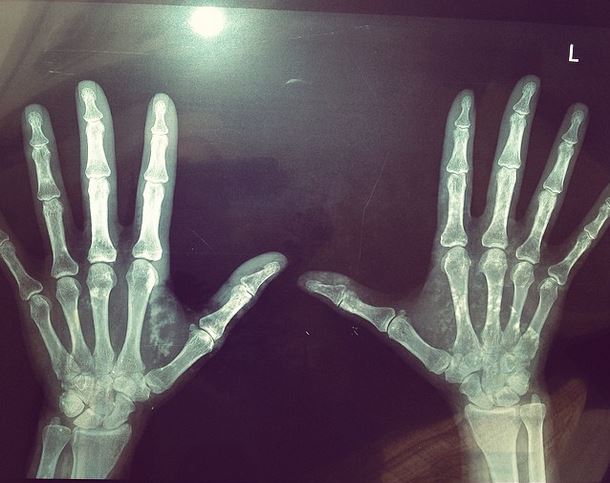

“Και μια και τα μοιραζόμαστε όλα εδώ μέσα, ορίστε τα χεράκια μου” έγραψε η γνωστή παρουσιάστρια στο instagram ανεβάζοντας φωτογραφία με την ακτινογραφία των χεριών της…

Ο λόγος για την Μαρία Μπακοδήμου, η οποία διευκρίνησε ωστόσο πως όλα είναι καλά.